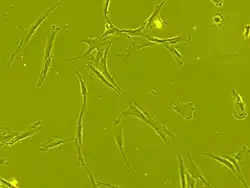

Stem cell transplantation is an important avenue for SCI research: the goal is to replace lost spinal cord cells, allow reconnection in broken neural circuits by regrowing axons, and to create an environment in the tissues that is favorable to growth.[78] A key avenue of SCI research is research on stem cells, which can differentiate into other types of cells—including those lost after SCI.[78] Types of cells being researched for use in SCI include embryonic stem cells, neural stem cells, mesenchymal stem cells, olfactory ensheathing cells, Schwann cells, activated macrophages, and induced pluripotent stem cells.[164] Hundreds of stem cell studies have been done in humans, with promising but inconclusive results.[151] An ongoing Phase 2 trial in 2016 presented data[165] showing that after 90 days, 2 out of 4 subjects had already improved two motor levels and had thus already achieved its endpoint of 2/5 patients improving two levels within 6–12 months. Six-month data was expected in January 2017.[166]

In March 2025, researchers reported that a paralyzed man stood for the first time after being injected of neural stem cells to treat his spinal cord injury. The first-of-its-kind study, which is not yet peer reviewed, is encouraging scientists to consider if reprogrammed stem cells can be used in the future to treat people who are fully paralyzed. Reprogrammed cells are adult cells that are reverted to an embryonic-like state, from which they can be coaxed to develop into other cell types.[173]